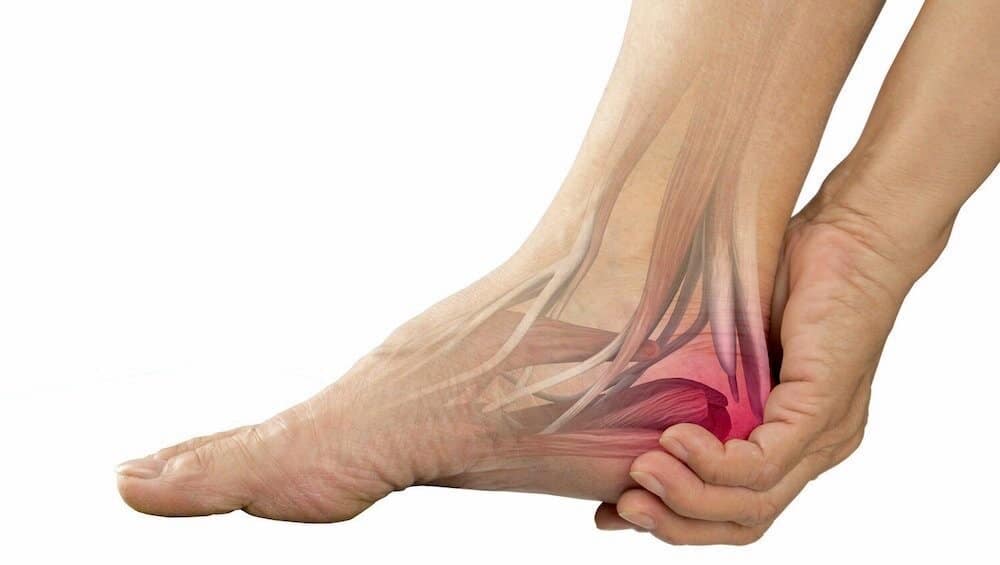

کلینیک تخصصی درمان خار پاشنه در تهران

خار پاشنه یک برآمدگی استخوانی است که در زیر استخوان پاشنه پا ایجاد می شود. این زائده معمولاً در اثر رسوب کلسیم و فشار طولانی مدت روی بافت های اطراف پاشنه پا به وجود می آید. خار پاشنه ممکن است بدون درد باشد یا با درد همراه باشد، به خصوص زمانی که بافت های اطراف […]

آیا درمان خار پاشنه با روش های خانگی امکان پذیر است؟

خار پاشنه پا التهاب پرده کف پا( فاشیای کف پا یا پلانتار) یکی از علل شایع درد پاشنه است.این بیماری به علت التهاب یک باند ضخیم است که از کف پای شما عبور می کند و استخوان پاشنه پا را به انگشتان پا متصل می کند (فاسیای کف پا ورم فاشیای کف پا که معمولا خار […]